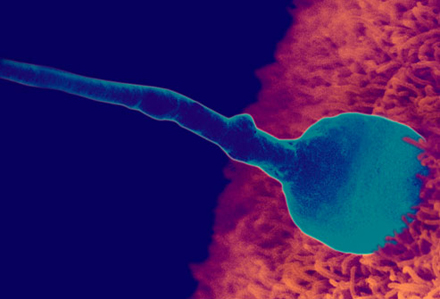

Daca ai un ciclu regulat, in ziua a 14-a (din cele 28) vei ovula. Acum este momentul propice pentru fertilizare. Odata ce un spermatozoid a fecundat ovulul, acesta isi inchide membrana si incepe sa se divida pe masura ce calatoreste spre uter, unde va continua sa creasca.